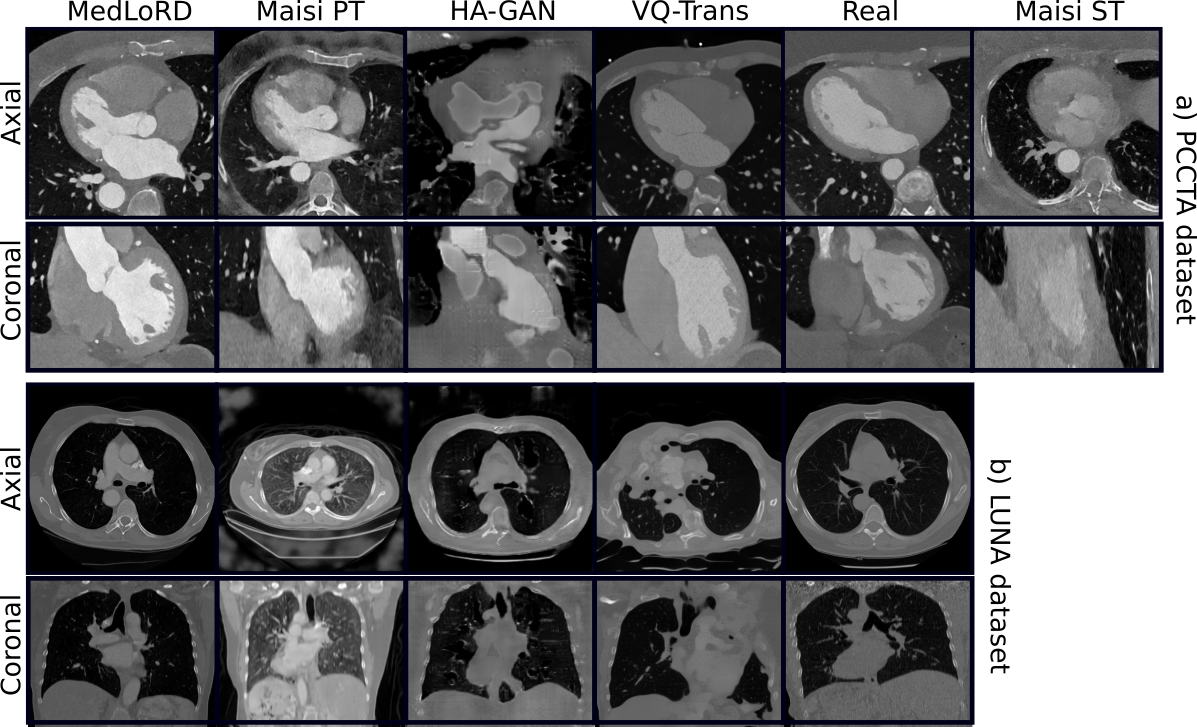

First, we conducted unconditional image synthesis. Fig. 2 shows representative samples from both the PCCTA and LUNA datasets. MedLoRD consistently generates high-quality, realistic images, preserving both global and local structural details. In contrast, other models exhibited unstable behavior, with some samples showing poor quality and heavy artifacts (e.g., loss of heart structures in MAISIST, poor realism in HA-GAN; see Fig. 2(a)). VQ-Trans and MAISIPT showed partial success, though the latter still displayed artifacts in PCCTA samples.

Refer to caption

Figure 2: Randomly selected unconditional samples for each method. Additional MedLoRD samples are provided in the supplementary material.

To quantitatively assess the quality of the generated images, we computed the FID between synthetic and real samples across different methods (Tab.  1). A 2.5D FID approach was employed, using a feature extraction model pretrained on RadImageNet [9]. MedLoRD achieved the best score on PCCTA (FID 1.50), and a competitive score on LUNA (FID 3.62), closely trailing MAISIPT (FID 3.33). These results indicate that our method produces highly realistic samples, particularly on structurally complex datasets such as PCCTA.

Finally, expert radiological assessment (Fig. 4) confirmed MedLoRD’s realism. Each dataset was evaluated by a domain expert following the criteria outlined in Fig. 4. For each dataset, 10 samples per model (including real data) were randomly selected, resulting in 60 shuffled samples that were anonymized and shown in random order to the radiologist, who graded all evaluation categories per sample. In the PCCTA dataset, MedLoRD outperforms all competing methods, with 8/10 synthesized samples labeled as indistinguishable from real ones, showcasing its strong generative capabilities. In the LUNA dataset, MedLoRD delivers strong performance, with only MAISIPT showing slightly higher radiological interest scores. However, 96% of the 40k CT images used to pre-train MAISIPT’s encoding model were chest scans, potentially giving it an advantage in lung image synthesis, due to a more comprehensive latent space. Together, these results highlight MedLoRD’s ability to generate anatomically accurate, high-quality 3D medical images, validated by both quantitative and expert evaluations.